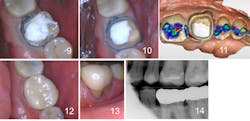

Figures 12, 13, and 14: Final zirconia crown cemented